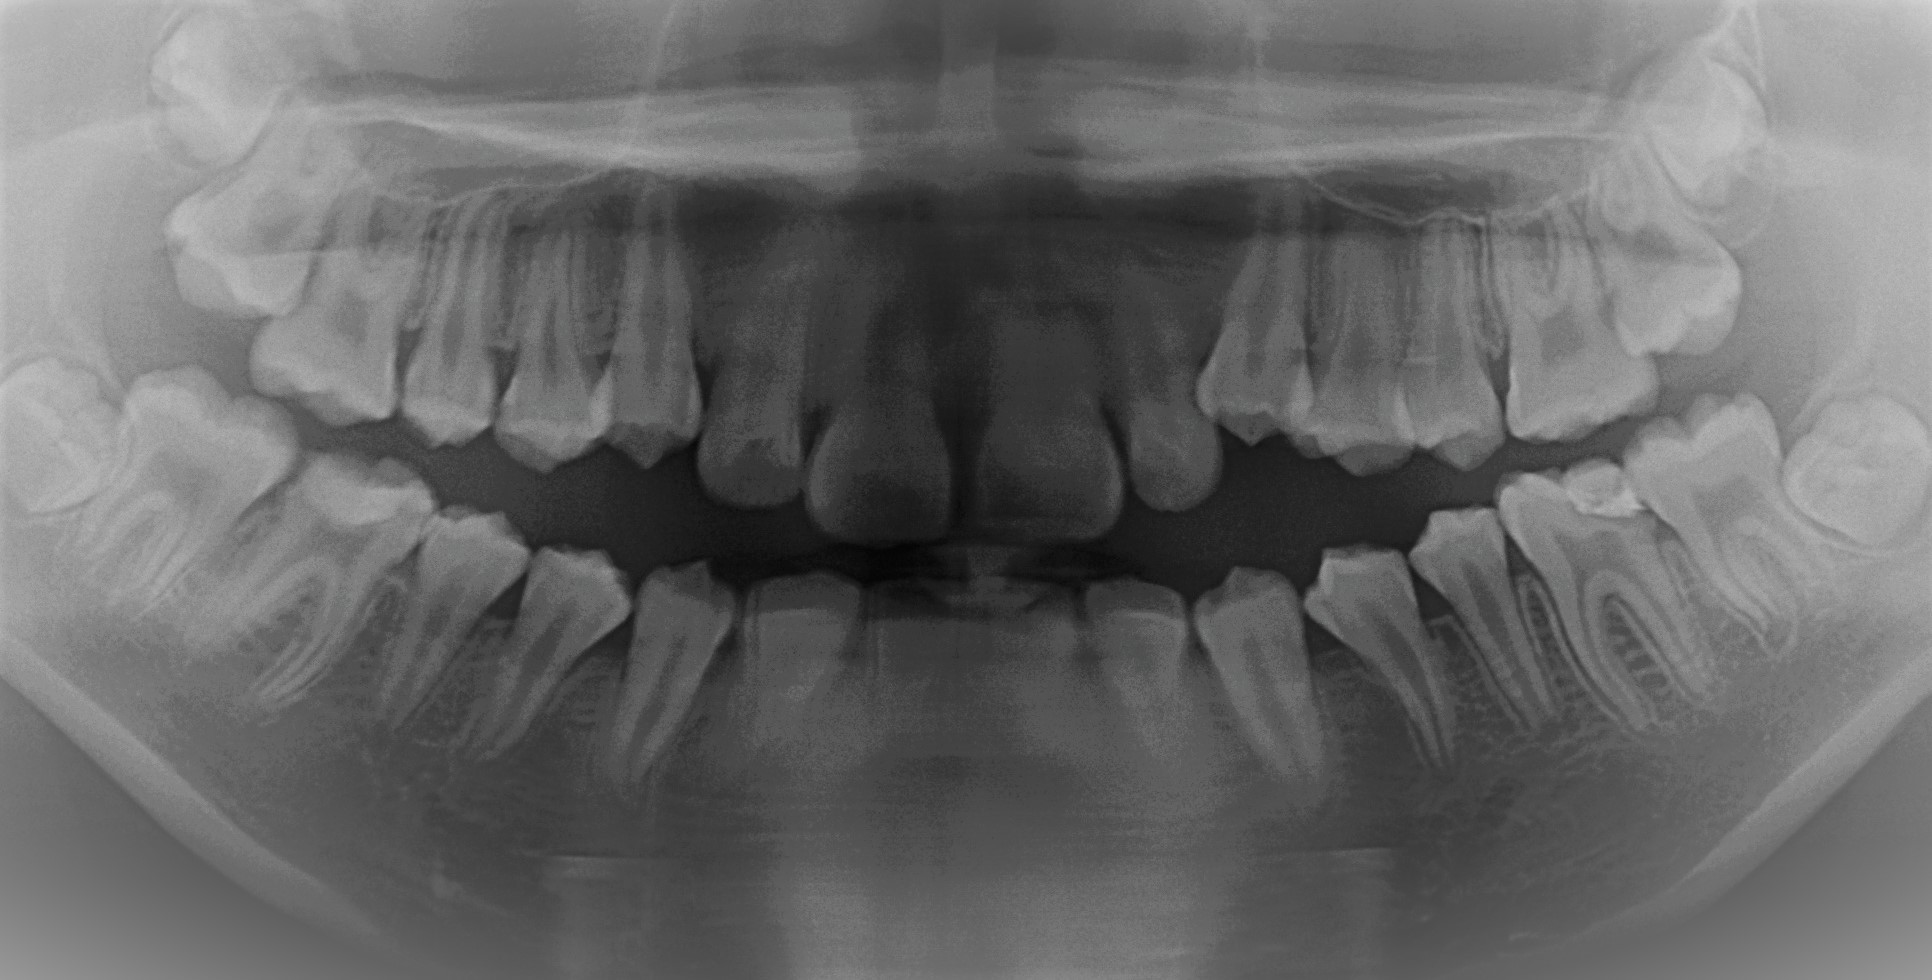

ドックスセメントを充填後です

経過を見たのち順次銀歯をはめていきました

自発痛などもなかったため経過は良好ですが、糖質制限や定期メンテナンスの継続が必須です